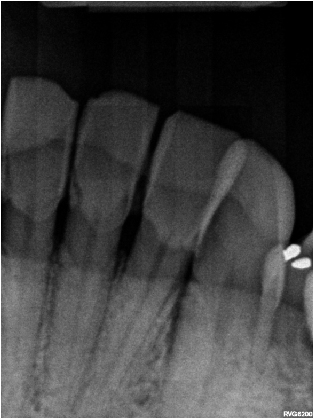

Before Treatment X-ray